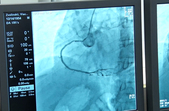

Для житомирської міської лікарні №2 ім. В.П. Павлусенка придбали ангіограф останніх моделей японської компанії Toshiba (Canon). Завдяки новому апарату пацієнти отримуватимуть медичну допомогу при лікуванні серйозних серцево-судинних захворювань.

«Практично старт даний. Перша коронарографія була проведена 25-го числа (жовтня), і на даний момент ми провели 14 коронарографій і 3 стентування. Це обладнання буде дозволяти проводити втручання на головному мозку, бо ми зараз говоримо про інфаркт, ми маємо запустити надання допомоги при гострому інфаркті, наступний етап це, звичайно, інсульти», – каже завідуючий міським центром ішемічних хвороб ЦМЛ №2 Олесь Кутній.